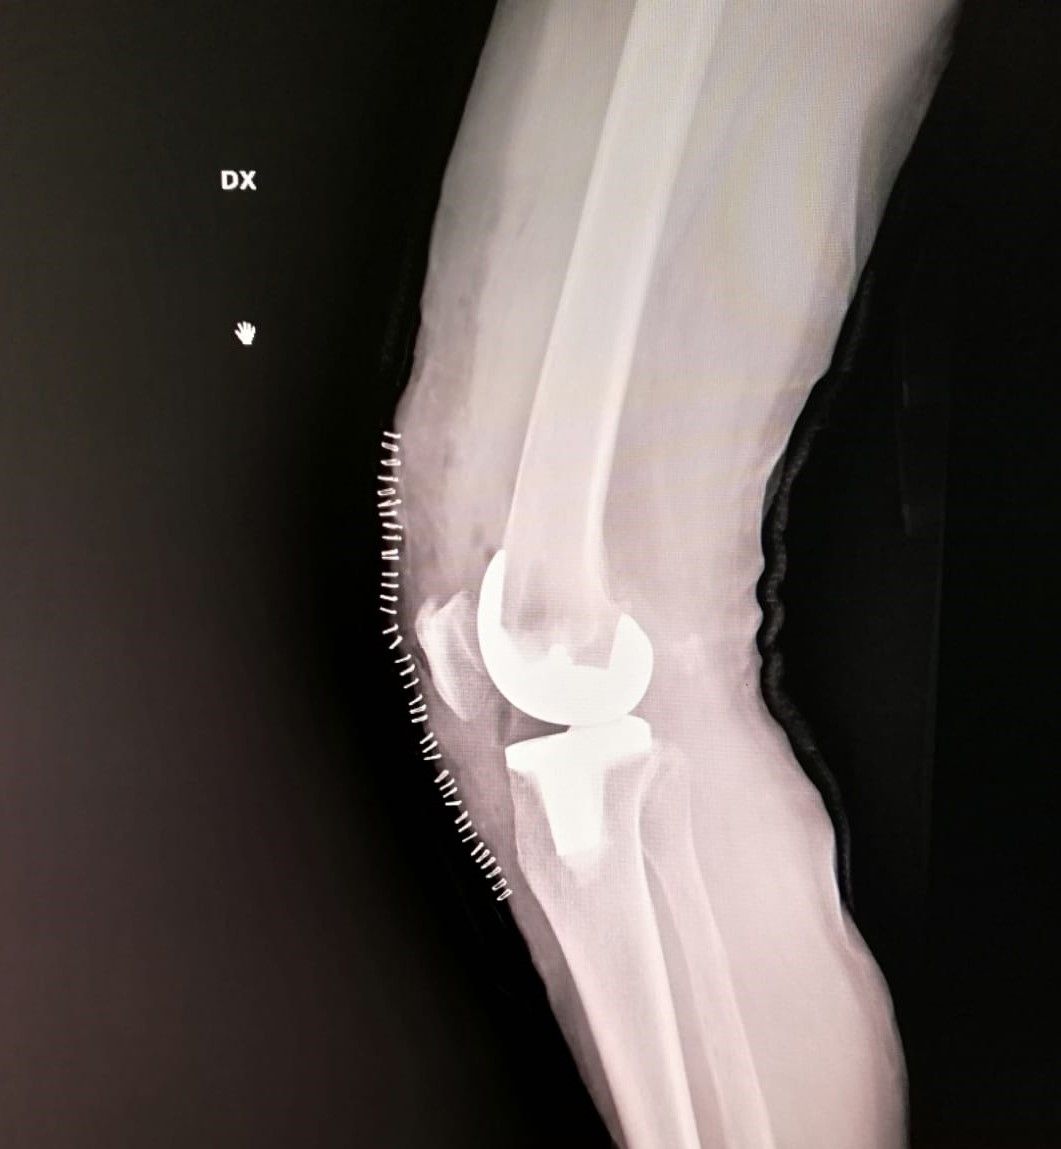

- protesi totale di ginocchio

- protesi mono-compartimentale del ginocchio